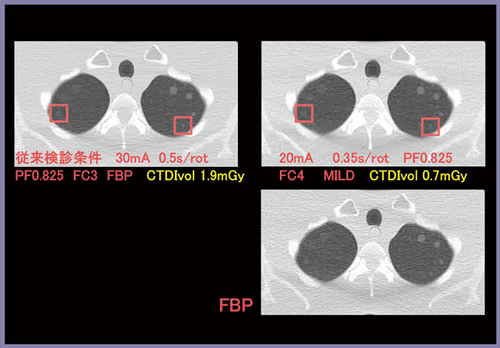

図6は,検出能優先での検討結果である。管電流を20mAまで低減し,管球回転速度も0.35秒と速くなったが,ノイズは増加するため,AIDR 3DのMILDを用いている。AIDR 3Dの強度が強くなるに伴い,再構成関数をFC3からFC4に調整した。

図6 検出能優先での検討結果

Δ270HU 4mm および Δ100HU 8mm検出は可能だが,信号の辺縁はFBPより劣る。